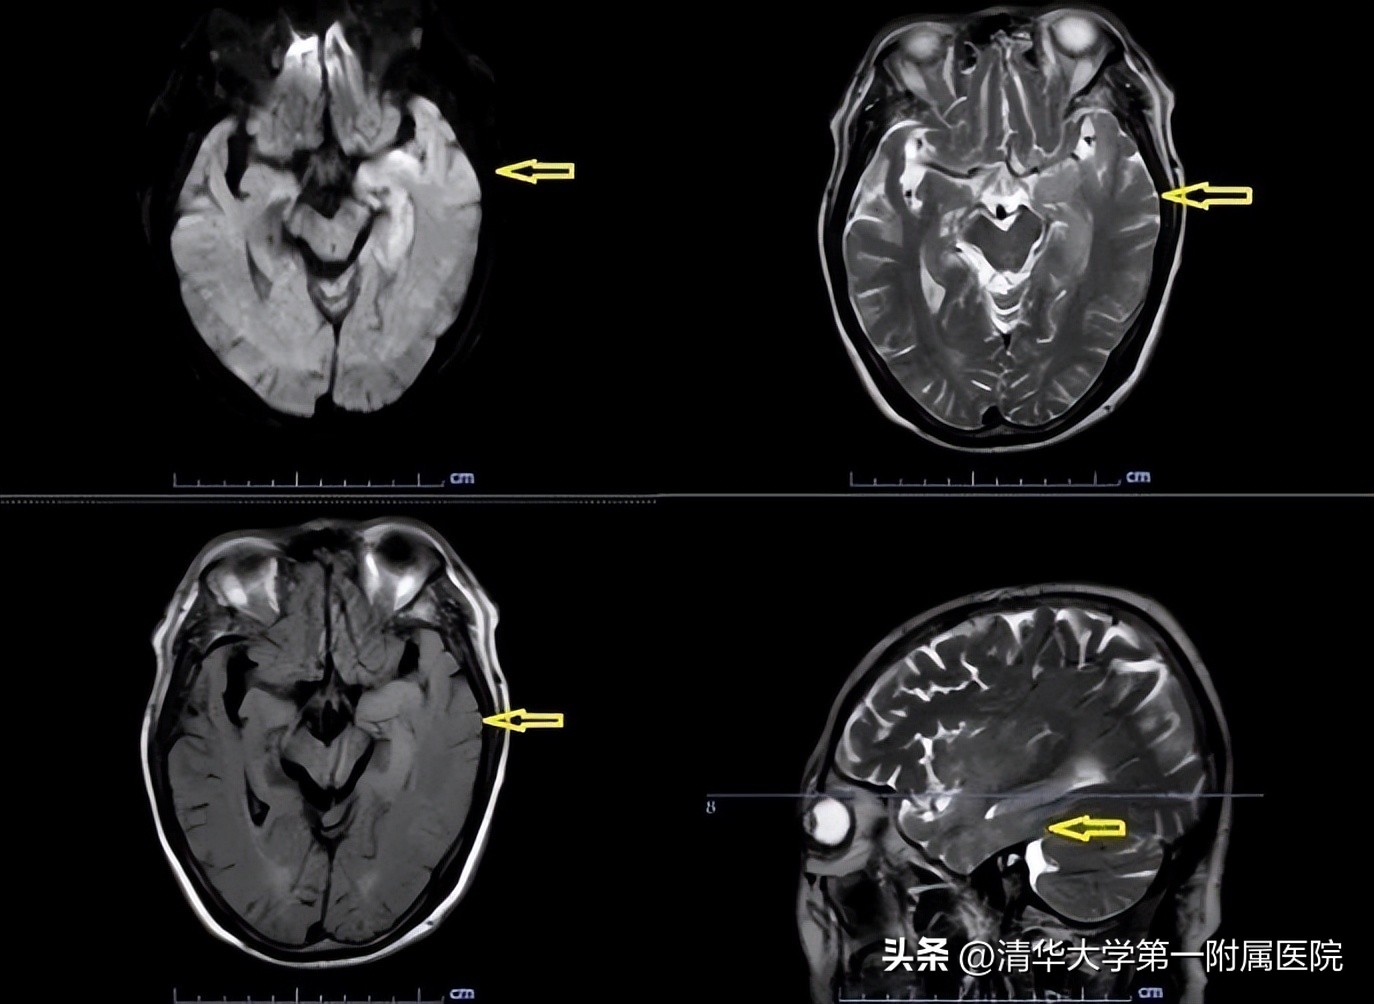

1月12日,北京华信医院(清华大学第一附属医院)神经内科监护室收治了一名发热10天,伴精神行为异常5天的老年患者。入院当天患者淡漠木僵、言语不能,全身可见散在出血点。经头部核磁共振显示左侧岛颞叶与海马区异常信号;脑电图显示额颞区慢波,左侧额颞区及蝶骨电极较多尖波、尖型慢波散发,偶可波及左半球。初步诊断:症状性癫痫(继发性癫痫)、脑炎。立即完善腰椎穿刺,脑脊液宏基因组测序提示I型单纯疱疹病毒感染。给予抗癫痫、抗病毒、脱水降颅压等对症治疗。